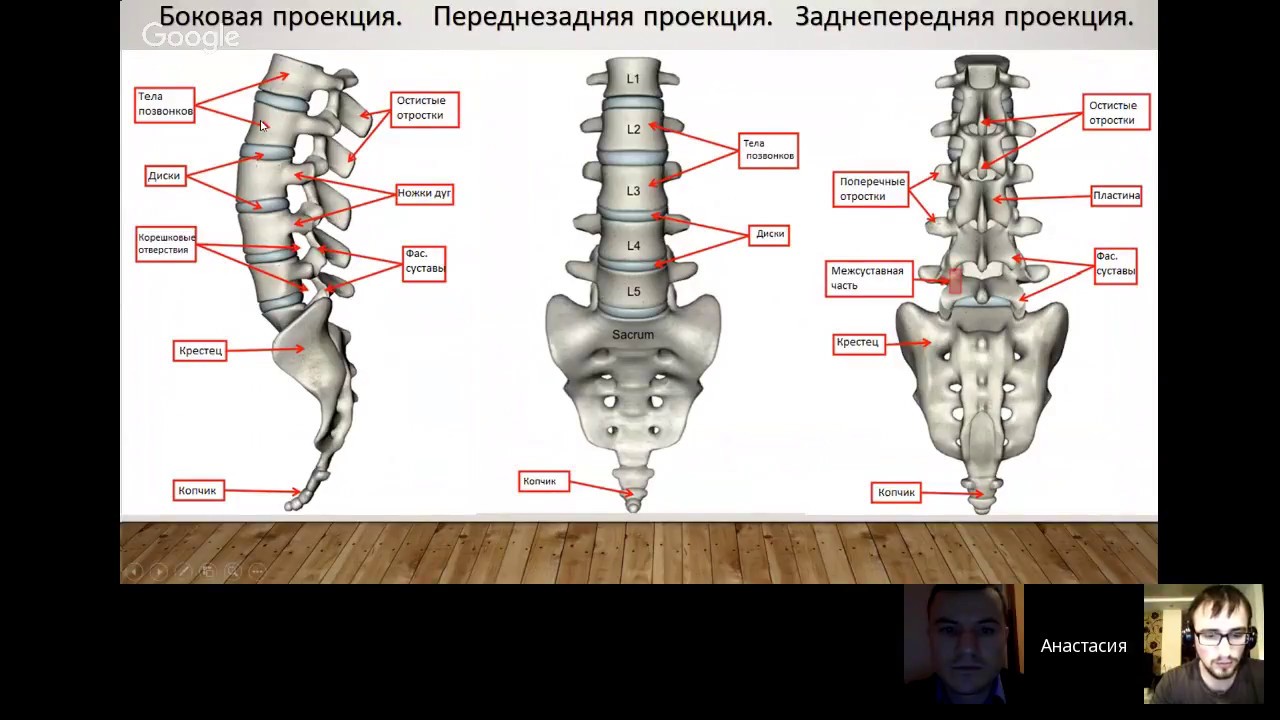

Отделы позвоночника для мрт схема фото и названия